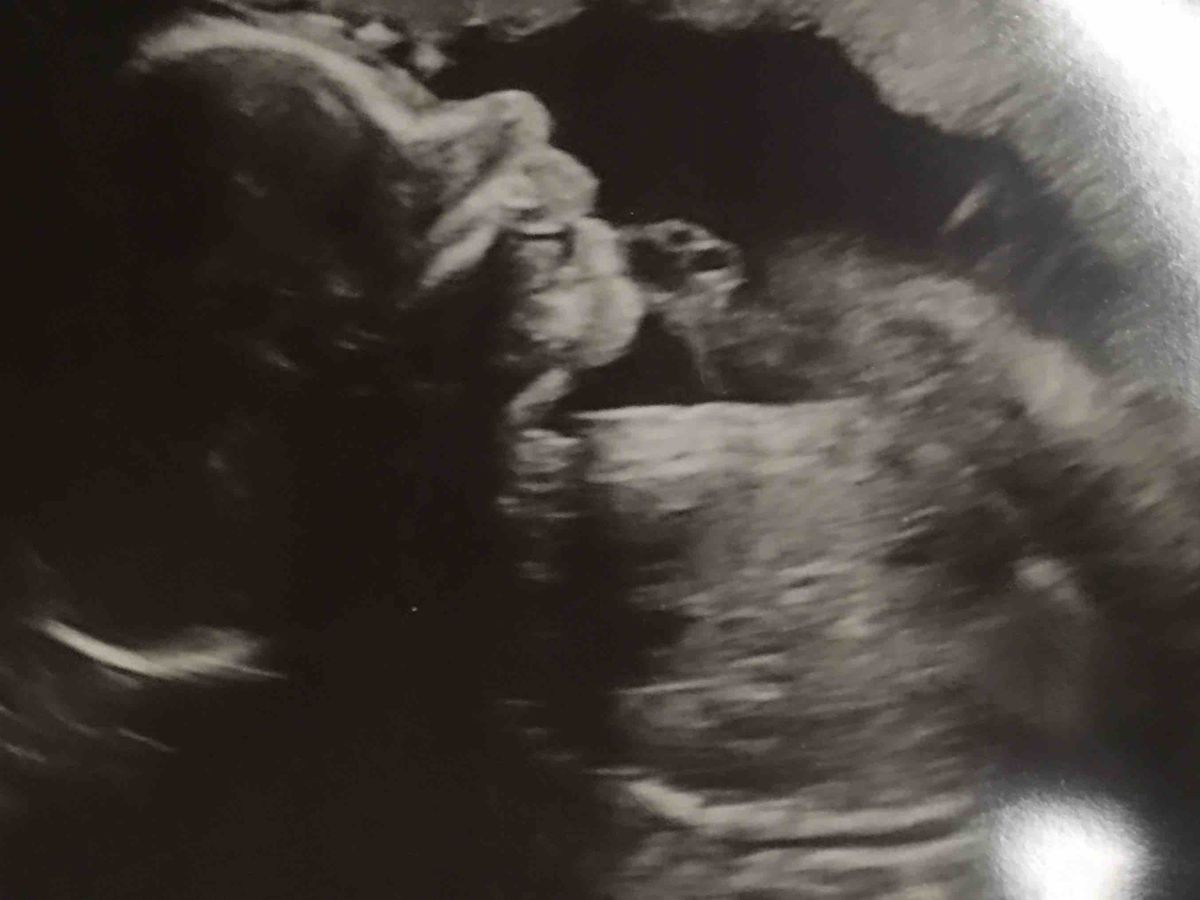

Samuel Grayson Woodward is due July 6th, when he arrives he will begin the fight of his life. He will have reparative surgery on his O, along with Open Heart surgery at some point after that. Although the road is uncertain we are certain that our God will keep this precious boy safe and heal his little body.